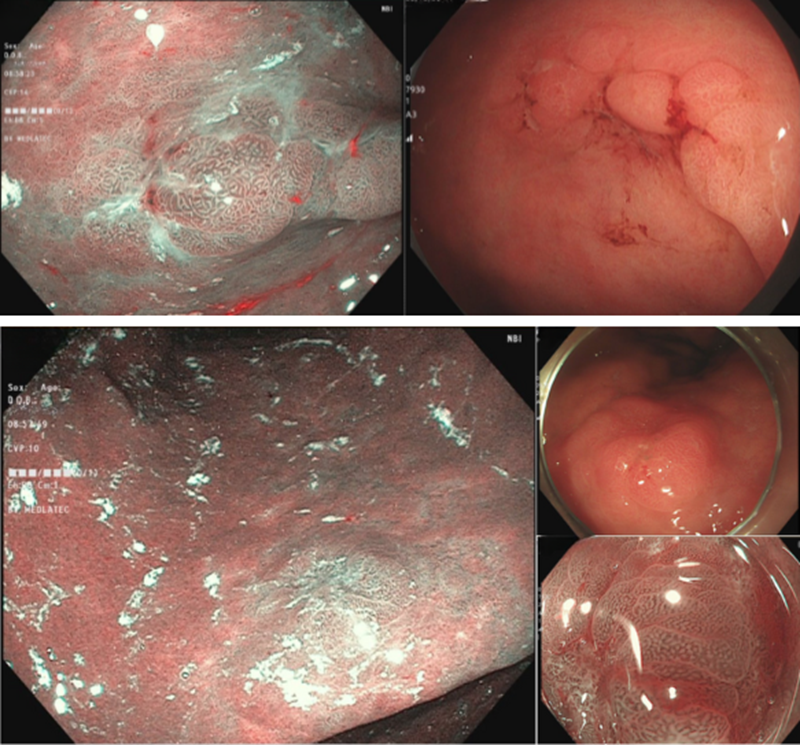

Hình ảnh tổn thương tại hang vị dạ dày và góc bờ cong dạ dày

Nội soi thực quản – dạ dày – tá tràng ghi nhận tổn thương tại hang vị dạ dày kích thước khoảng 3cm và vùng góc bờ cong dạ dày kích thước 1,5cm. Sinh thiết mô bệnh học cho kết quả loạn sản độ cao.